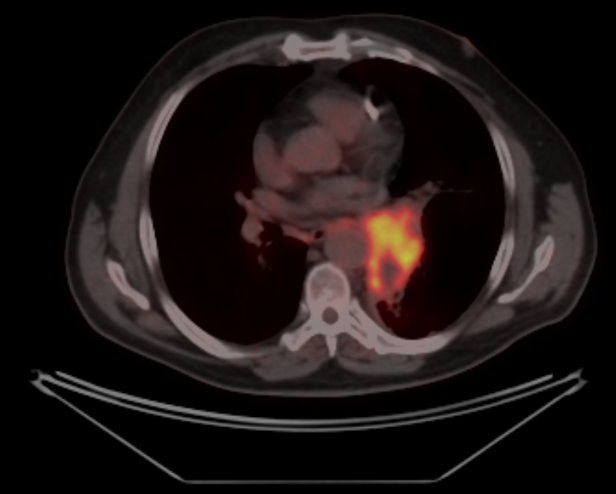

Заключение ПЭТ-КТ с ФДГ от 29.03.2022г:

- картина центральной опухоли левого легкого с признаками обструктивного пневмонита, мтс с поражением ипсилатеральных и подкаринальных лимфоузлов.

В воротах левого легкого определяется метаболически активный опухолевый узел с вовлечением главного, нижнедолевого, частично верхнедолевого бронхов, общими наибольшим размерами около 83 мм в аксиальной проекции и до 81 мм в краниокаудальной проекции, SUVmax=21.41. Опухоль располагается на расстоянии около 30 мм от киля трахеи с вовлечением левой легочной артерии (обхват около 50%) и тесным прилеганием к нисходящей аорте. Окружающая паренхима левого легкого с признаками воспаления. В правом легком очаговая и инфильтративная патология легких не определяется.Определяются метаболически активные медиастинальные лимфоузлы, наибольшими размерами/накоплением РФП: подкаринальной группы (7) до 10 мм, SUVmax=7.49; субаортальной группы (5) до 8 мм, SUVmax=4.70. Лимфоузлы ворот левого легкого четко не дифференцируются, вероятнее сливаются с основной опухолевой массой.

В воротах левого легкого определяется метаболически активный опухолевый узел с вовлечением главного, нижнедолевого, частично верхнедолевого бронхов, общими наибольшим размерами около 83 мм в аксиальной проекции и до 81 мм в краниокаудальной проекции, SUVmax=21.41. Опухоль располагается на расстоянии около 30 мм от киля трахеи с вовлечением левой легочной артерии (обхват около 50%) и тесным прилеганием к нисходящей аорте. Окружающая паренхима левого легкого с признаками воспаления. В правом легком очаговая и инфильтративная патология легких не определяется.Определяются метаболически активные медиастинальные лимфоузлы, наибольшими размерами/накоплением РФП: подкаринальной группы (7) до 10 мм, SUVmax=7.49; субаортальной группы (5) до 8 мм, SUVmax=4.70. Лимфоузлы ворот левого легкого четко не дифференцируются, вероятнее сливаются с основной опухолевой массой.